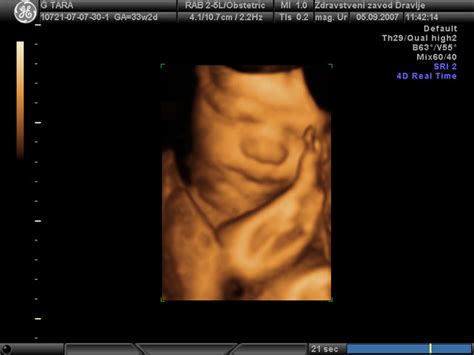

Zunanji obrat je postopek, pri katerem ginekolog s pomočjo ultrazvoka in rok skuša otroka obrniti v glavično lego. Ta poseg se običajno izvaja med 37. in 38. tednom nosečnosti, ko je otrok že dovolj razvit, da bi lahko preživel zunaj maternice v primeru, da bi obrat sprožil prezgodnji porod. Cilj je izogniti se tako vaginalnemu porodu v medenični vstavi kot tudi načrtovanemu carskemu rezu, ponujajoč varno alternativo.

Postopek zunanjega obrata se lahko v različnih porodnišnicah nekoliko razlikuje. Vendar pa osnovni principi ostajajo podobni. Pred samim obratom se izvede ultrazvočni pregled, s katerim se oceni lega otroka, količina plodovnice, velikost otroka in maternične medenice. S kardiotokografijo (CTG) se spremljajo srčni utripi otroka in morebitni popadki.